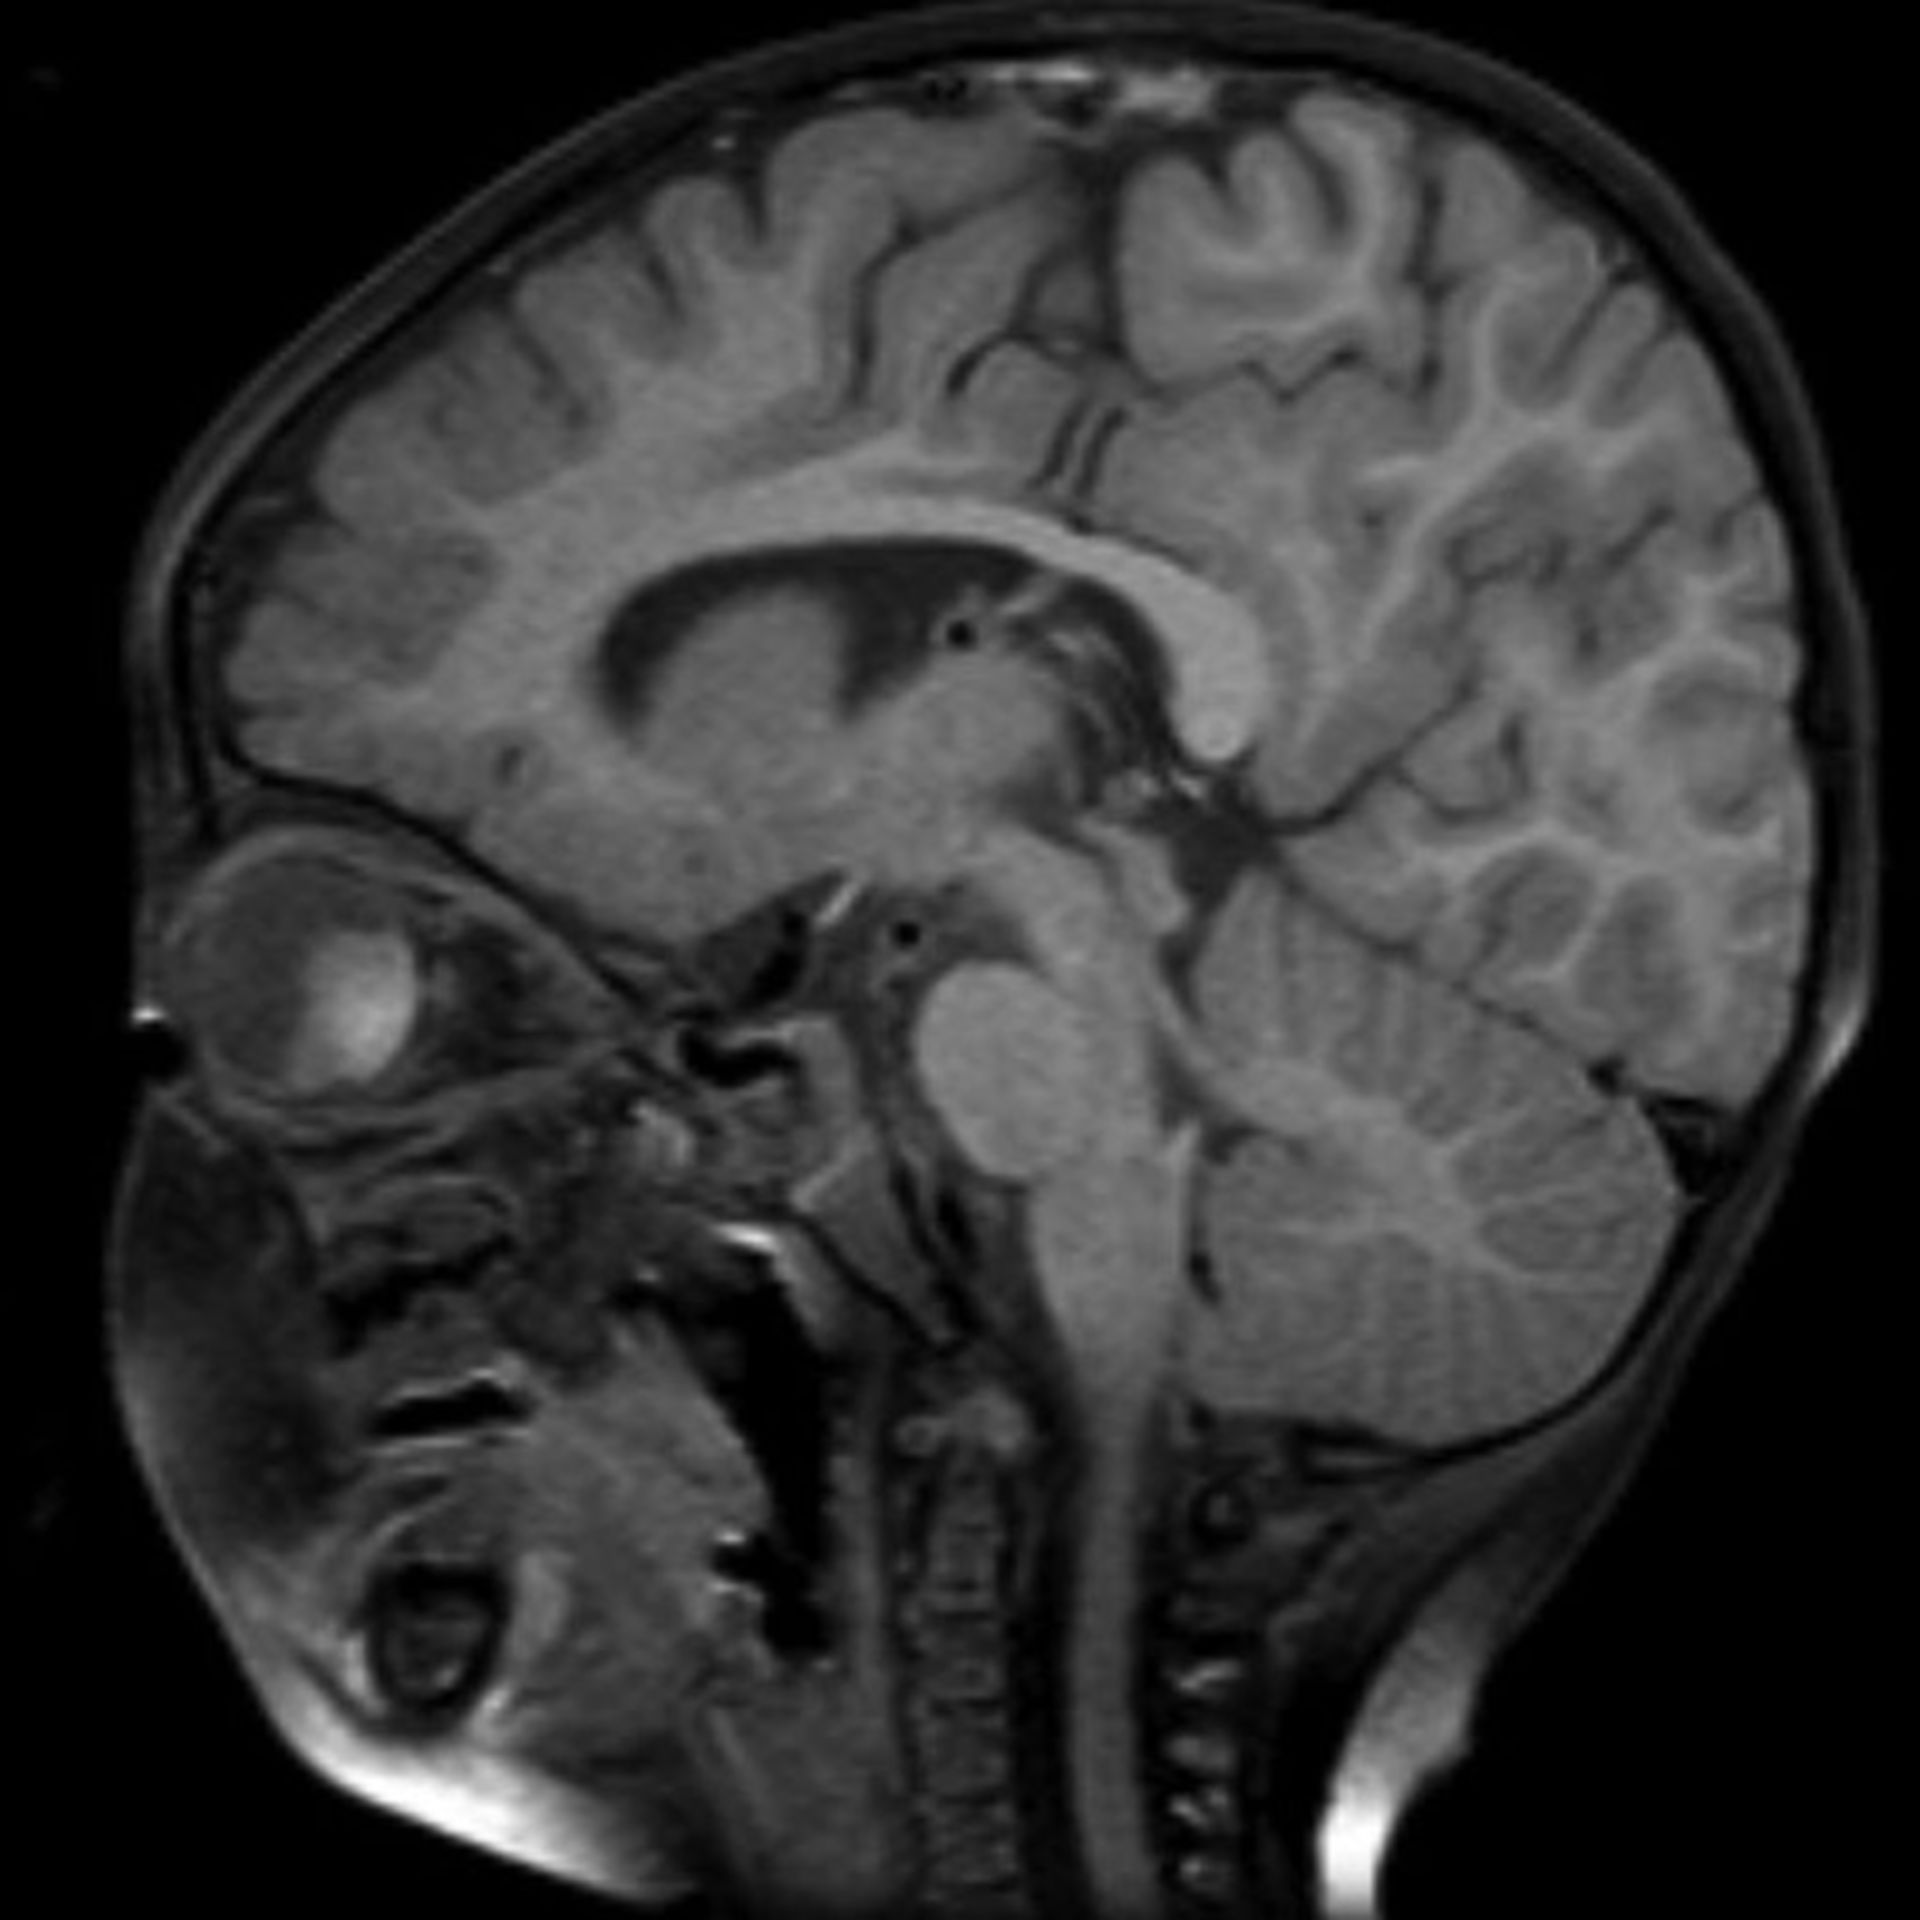

(16/34) MRT Schädel in Sagittalebene, T₂‐gewichtet – DocCheck MRT Bilder-Hubbel-??? Hilfe (Kopf)

Glioblastom in der MRT,T1-gewichtet mit Kontrastmittel, sagitaler Schnitt aus dem KGU | Kampf … MRT eines Bandscheibenvorfalls an der LWS – Lizenzfreies Bild – #15202613 | Bildagentur PantherMedia